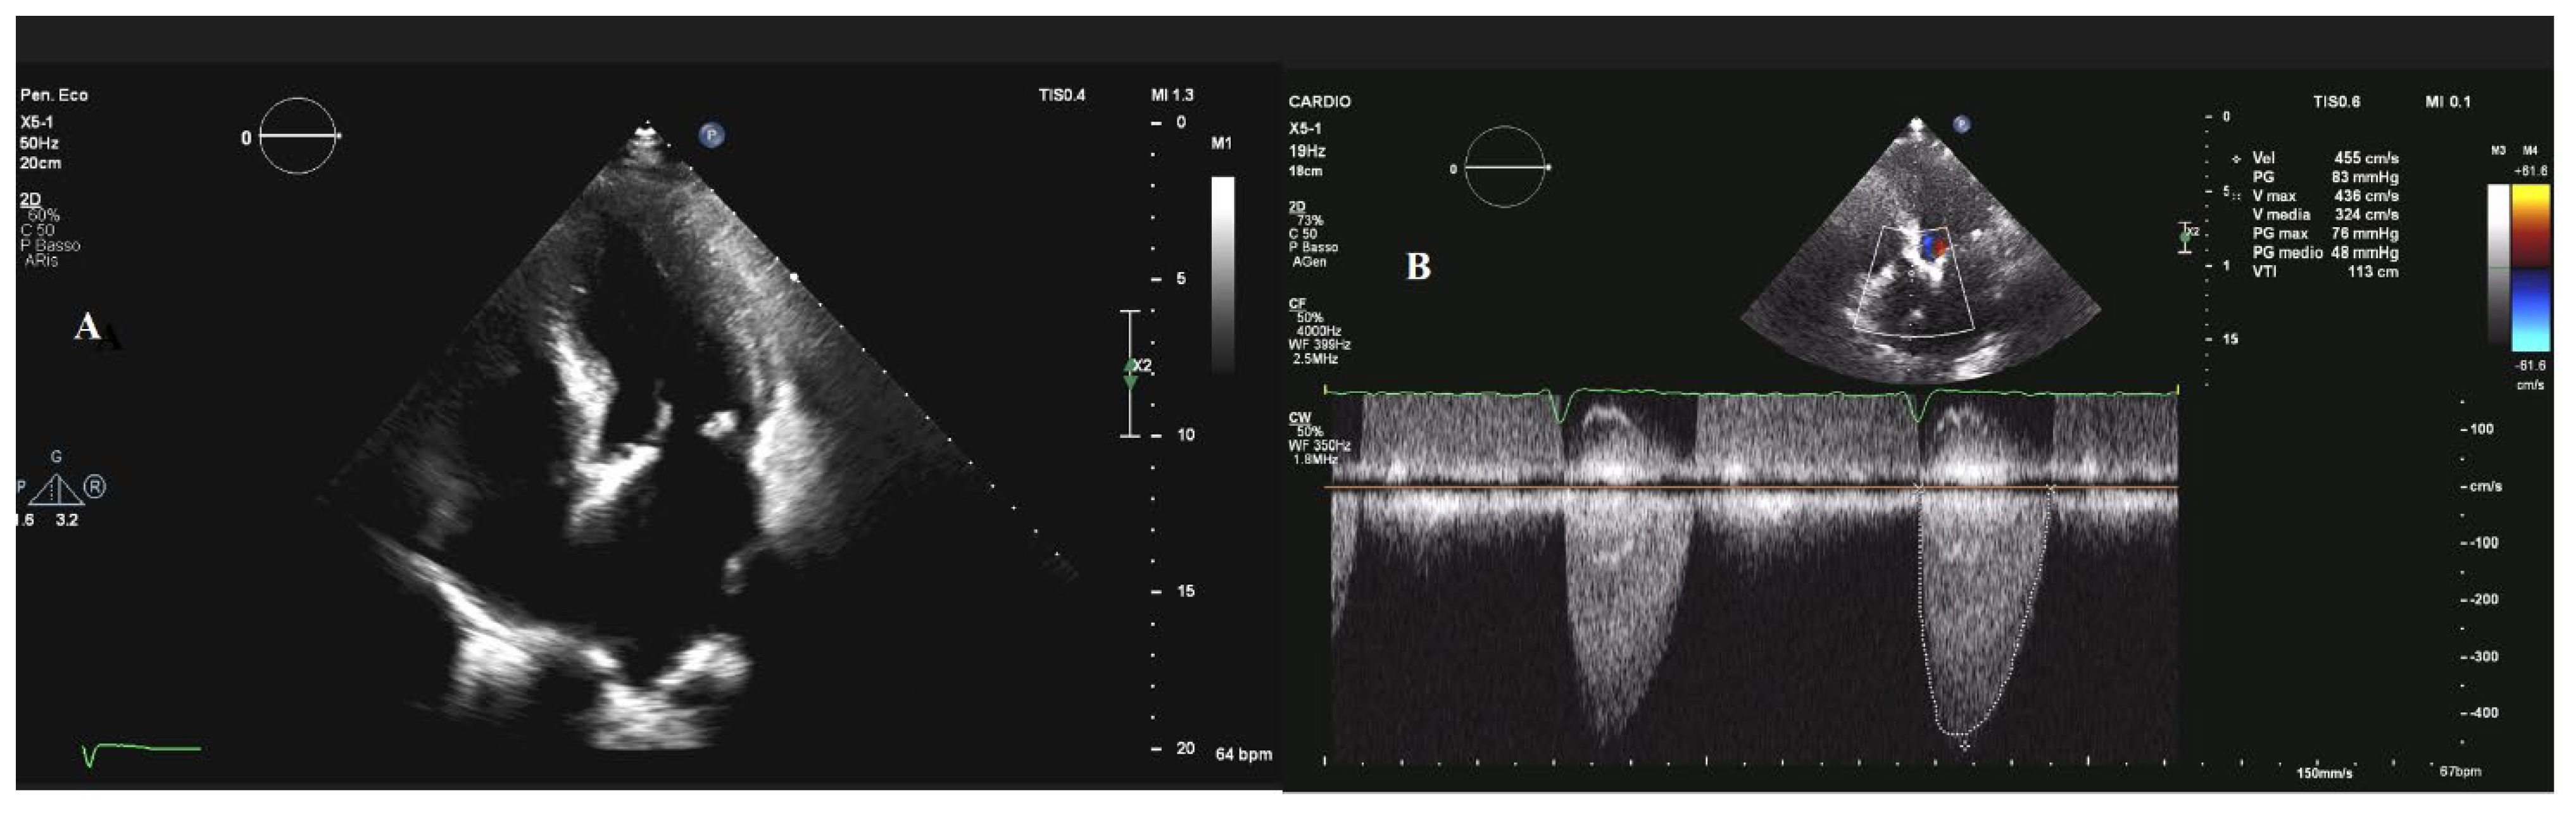

2. Aortic Stenosis

4. Mitral Stenosis

5. Mitral Regurgitation